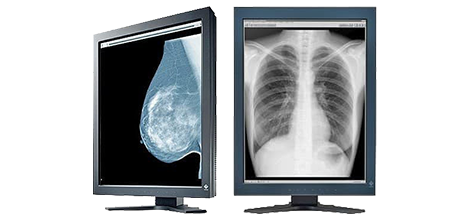

- Negatoskopy

- Monitory Medyczne